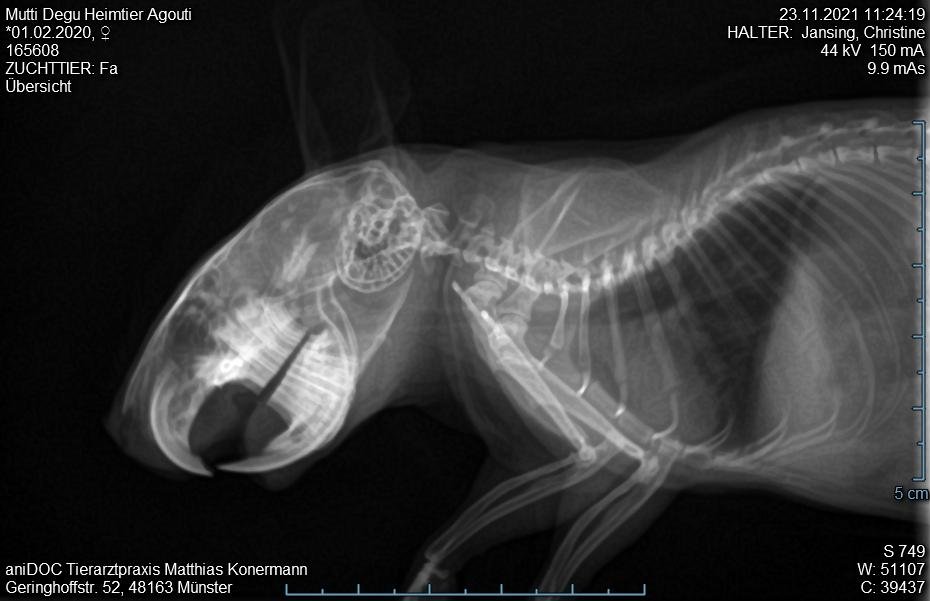

- Mutti_Degu_2021-11-23_11-24-19_Uebersicht.jpg (61.49 KiB) 3055 mal betrachtet

3. Tierarztbesuch am 23.11. Tier merklich mitgenommen, laute Atmung, nun auch beim Abhören der Lunge. Gewichtsverlust etwa 25-30 g. Sehr schwere Flankenatmung. Röntgenbild unter Gasnarkose. Tierarzt sieht nix drauf, Zähne sind aber gut. Verdacht auf Bauchfellentzündung. Neues AB borgal/riketron 24%, 2 Mal täglich 0.5 ml. Dachte, das Tier überlebt die Nacht nicht. Aber Verbesserung seit dem 25.11. Tier frisst wieder, ist bei 189g.